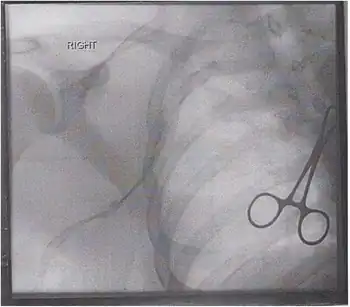

| Anterior view of right upper limb and thorax | |